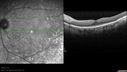

Ocular Lymphoma - non-Hodgkins - B-Cell - OCT shows multifocal sub-RPE masses 437 viewsMultifocal sub-RPE lesions in the left eye of a patient with history of Non-hodgkins B-cell Lymphoma last active 2 years agoMar 09, 2017

Ocular Lymphoma - non-Hodgkins - B-Cell - OCT shows multifocal sub-RPE masses 508 viewsMultifocal sub-RPE lesions in the left eye of a patient with history of Non-hodgkins B-cell Lymphoma last active 2 years agoMar 09, 2017